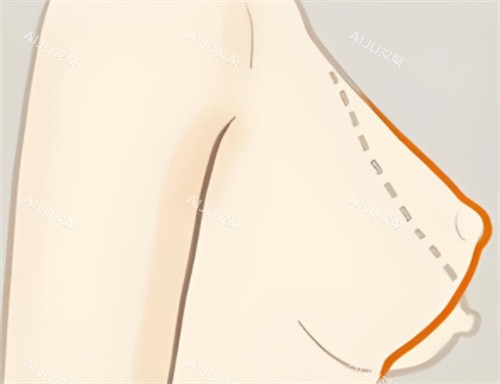

无锡李建东维维提升手术可信吗?3mm小创口切口+筋膜层复位,出血少修复快,疤痕藏在乳晕边缘隐形无痕!

传统手术靠“拉皮”,把下垂的皮肤往上拽,但皮肤有弹性极限,拽得越紧,反弹越快。维维提升的“狠活”在于:通过3mm的小创口切口(比一粒米还小),用可吸收线材更准一些找到乳腺下的筋膜层和悬韧带。打个比方,就像给下垂的吊灯重新挂好挂钩——不是单纯拉绳子,而是加固吊灯的支架,让胸部从“软塌塌”变成“有筋骨”。

传统乳房悬吊术需要在乳晕和下皱襞开双切口,总长度8-10cm,术后疤痕像“两条蜈蚣”。维维提升的切口仅2.5-3cm,藏在乳晕边缘,色素遮盖+精细缝合,6个月后疤痕淡化为一条浅浅的白线,穿比基尼、低领衣服完全无压力。